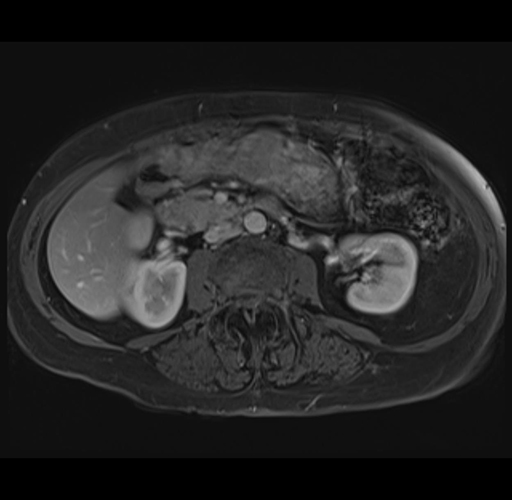

MRI T1

Imaging analysis

Based on your CT findings, which issue(s) would give reason for "planned slowing down moment(s)" in this case?

Considering a standard right hepatectomy procedure, what step(s) of the operation would you do differently in this case?